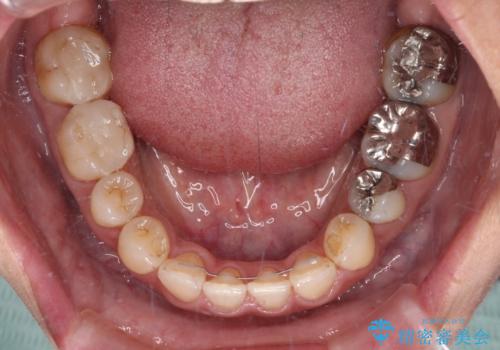

下顎前歯は2本欠損しており、それが原因で隙間ができていました。

また、その影響で上下歯列がアンバランスとなっており、上下前が非接触となっていました。

上顎左右第1小臼歯を抜歯したことで、隙間が閉じた下顎歯列の位置まで前歯を引っ込ますことができたため、口の閉じにくさを解消することができました。